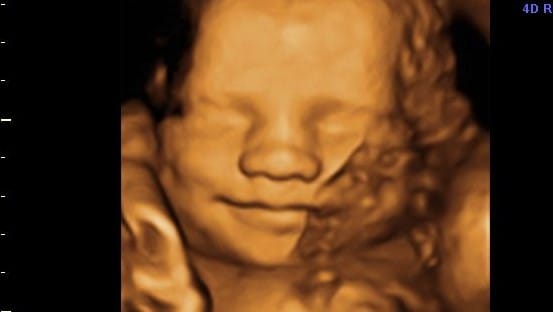

Ultrassom 3D ou 4D(?) se refere a estas imagens que parecem moldes de cera com formato de feto dentro do útero, e são uma produção virtual cibernética e criativa que brota desse imenso campo das fantasias humanas.

Nas ultrassonografias o programa “mente”, suaviza as bordas, preenche de forma automática as lacunas e falhas que o ultrassom não capta, acrescenta um colorido que os sons não reconhecem, oferecendo uma mentira que a todos agrada e satisfaz, além de aliviar as angústias e fantasias dos pais. Criamos um método baseado no falseamento das formas e na homogeneização dos contornos, mas curtimos essa mentira na medida que ela nos alivia a alma e diminui o peso das nossas ansiedades.